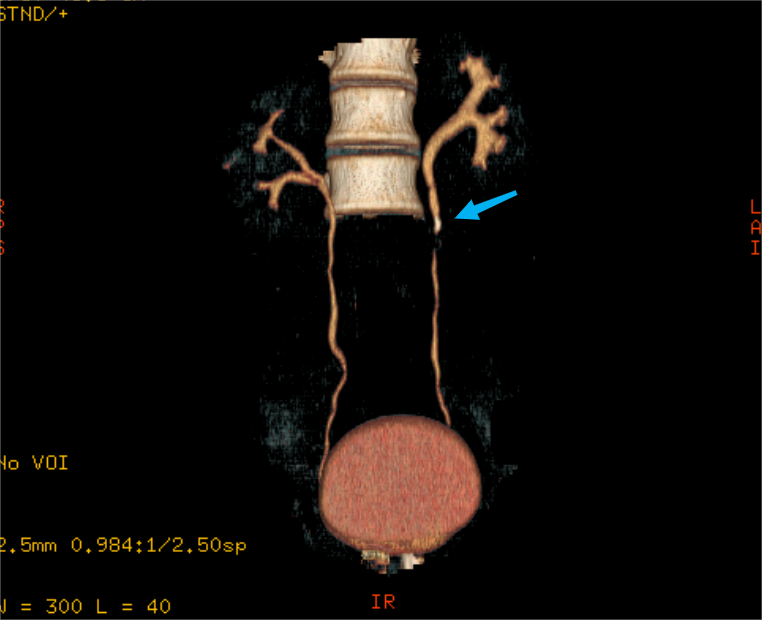

到了医院一做彩超,真相大白:左侧输尿管上段长了个 7 mm*5 mm 大小的结石,左肾还有轻度的积水。

其中,体外冲击波碎石术是利用体外产生的冲击波聚焦于体内的结石使之粉碎,继而将其排出体外达到治疗目的的治疗方法。

搞清楚情况的杨先生接受了手术,手术顺利完成。